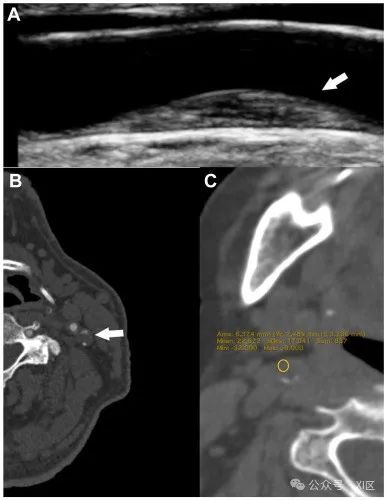

LRNC是一种异质组织,由富含脂质的巨噬细胞、胆固醇晶体、平滑肌泡沫细胞死亡以及血浆衍生脂质堆积形成,并由内膜细胞外基质大分子拴住。LRNC在动脉粥样硬化斑块的进展和易损性中起着关键作用。2017年发表的一项对16项研究的荟萃分析显示,CT血管造影显示存在低衰减斑块的患者发生同侧脑血管事件的风险几乎是其他患者的三倍,与血管狭窄程度无关。2013年发表的一项系统回顾和荟萃分析显示,LRNC可预测无症状受试者的卒中或TIA。MRI因其卓越的软组织对比度被认为是评估LRNC最敏感的方式。相反,由于IPH和LRNC的CT值明显重叠,CT扫描通常被认为灵敏度较低。同样,US检查也被认为不太适合用于区分出血和脂质成分(图3)。

图3超声(US)检查(A)和CT扫描(B、C)显示富脂质坏死核心的实例。(A)一名同侧缺血性卒中的62岁女性左侧颈总动脉非硬化性颈动脉斑块,斑块内有一个富脂坏死核心(LRNC)和厚纤维帽(FC)。(B)一名有症状的82岁男性左侧颈内动脉中的低衰减、亚闭塞斑块,其平均CT值为43 HU,类似于LRNC。(C)同侧缺血性卒中的72岁男性右侧颈内动脉中的低衰减、亚闭塞斑块,平均CT值为22 HU。然而,由于脂质和出血成分的CT值重叠,因此不能排除斑块内出血(IPH)的可能性。斑块形态